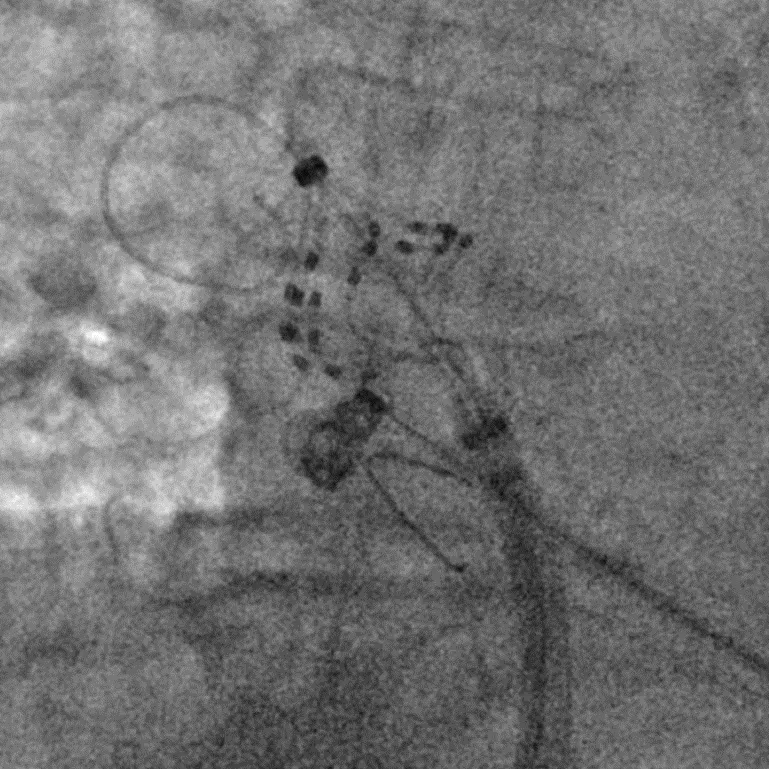

手术在全麻下进行,消融策略涵盖双侧肺静脉、左房后壁及上腔静脉,总计消融73个位点,累计消融时间仅146秒。术中活化凝血时间(ACT)维持在250-300秒,未出现并发症。消融结束后,患者仍为房颤心律,经电复律成功转为窦性心律,手术顺利完成。

六瓣花导管呈网篮及花瓣形态放电

LSPV消融及前后电位对比

LIPV消融及前后电位对比

RSPV消融及前后电位对比

RIPV消融及前后电位对比

后壁消融及前后电位对比

上腔静脉消融及前后电位对比